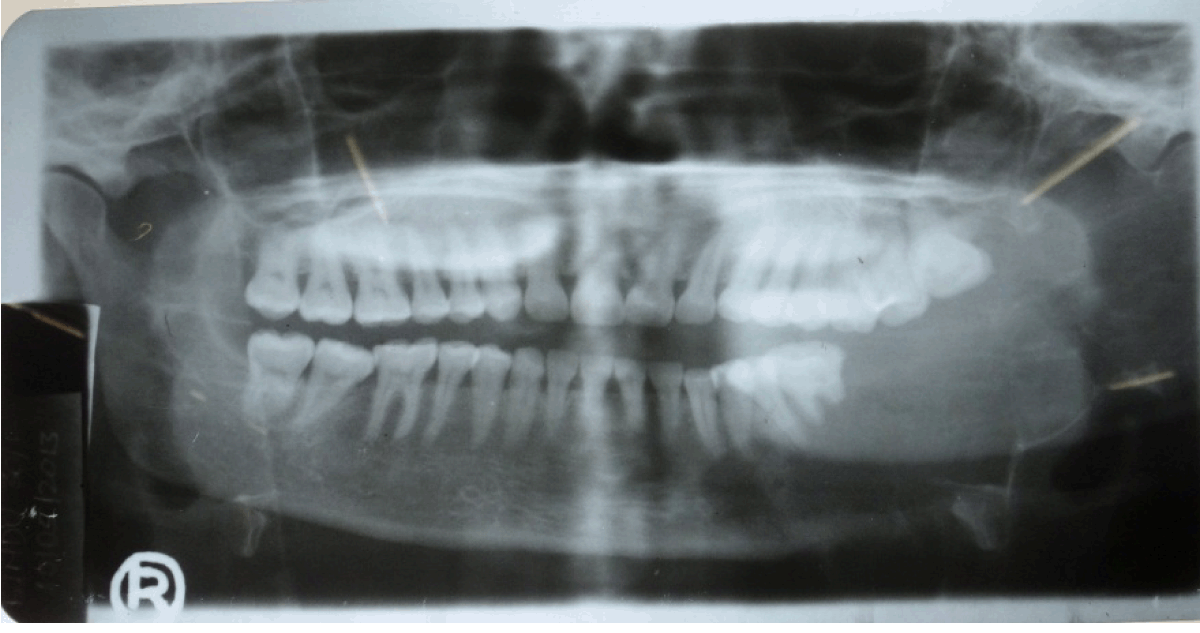

The orthopantomograph (OPG) showed a well-defined radiolucency involving the left body, angle and ramus of the mandible (Figure 3). The OPG revealed root resorption of left lower first molar tooth. Plain and contrast axial and coronal computed tomography (CT) scans showed a lobulated expansile lytic lesion involving body, ramus, and coronoid process of mandible measuring 6.3x8.3x10 cm in size, with thinning of the cortices (Figure 4). A chest radiograph ruled out the presence of any metastatic deposits. An incisional biopsy was done and the tissue was sent for histopathologic examination. The histopathology was consistent of ameloblastic carcinoma (Figure 5). On the basis of the histopathology report, left hemimandibulectomy was done taking a safe margin of 2 cm and the defect was reconstructed using Titanium reconstruction plate. Chemotherapy and radiotherapy was not advised. The patient is under regular follow-up. No recurrence or metastases reported during the follow-up period.

Figure 3: Orthopantomogram showing the lesion.